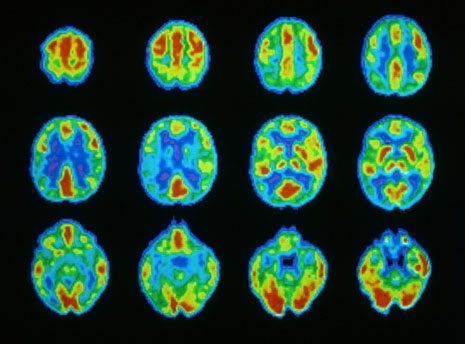

¿Qu’est-ce qu’un neurotransmetteur ? Les neurotransmetteurs ont été découvert en 1921 par le biologiste Otto Loewi, qui gagnera plus tard le prix Nobel pour son travail. Jusqu’à lors, on croyait que la communication inter neuronale (entre les neurones) était le fruit d’une communication électrique. Loewi a découvert que ce concept était erroné, en démontrant que les neurones communiquent entre eux grâce à la libération de substance chimiques, appelées neurotransmetteurs, Depuis 1921 jusqu’à aujourd’hui, on a découvert plus de 60 types différents de neurotransmetteurs.

Nous pouvons définir les neurotransmetteurs comme les biomolécules nécessaires au transport de l’information d’un neurone à l’autre au moyen du processus de synapsis.

Un bon fonctionnement de nos neurotransmetteurs nous apporte un équilibre régulier dans toutes nos fonctions du système nerveux. Il arrive que la production ou la synthétisation de différents neurotransmetteurs, dû à notre environnement ou à notre bagage génétique, ce qui peut entraîner des désordres ou des troubles physiques et psychologiques.